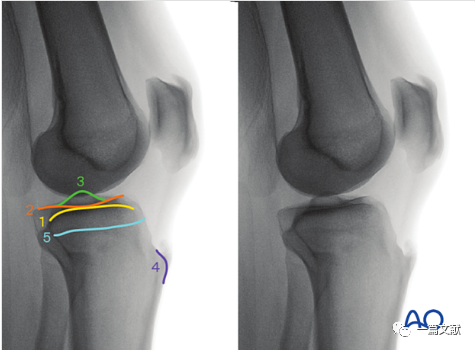

1)在标准正位的基础上,将C臂机向头端倾斜10°,抵消胫骨平台的后倾角,使射线完全平行于胫骨关节面。如下图:

2)头倾10° 正位的评估:1、胫骨平台关节线位于图像中央;2、内侧和外侧平台关节线分别显示位一根较粗的线。如下图:

3)解剖标志的识别:如下图:1、外侧平台关节面(凸面)2、内侧平台关节面(凹面)3、髁间脊4、闭合的骨骺线

4)头倾10° 正位片的意义:1、评估内侧和外侧平台复位情况;2、检视是否存在突入关节的内植物。